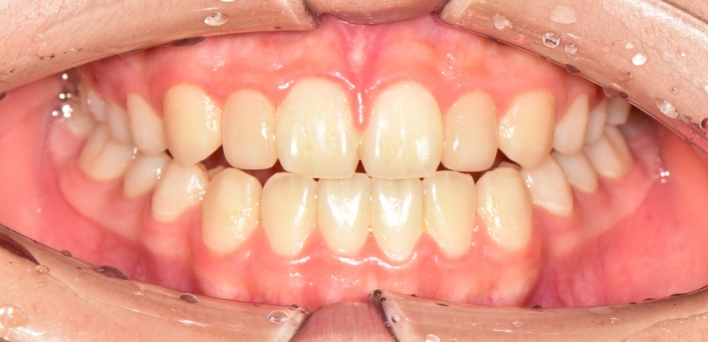

※ 더서울치과의원은 의료법을 준수하며 위 케이스는 실제 환자의 동의를 얻은 사례로 치료 전, 후가 동일한 환경에서 촬영되었습니다.

환자 케이스에 따라 부작용이 발생할 수 있습니다. 이 부분은 의료진의 충분한 상담과 체크를 통해 예방하고 줄일 수 있습니다.

[심미치료 부작용] 시술 후 치아 시림, 보철물 파손 등의 부작용이 발생할 수 있어 개인별 치아 상태에 따른 정확한 진단과 사후 관리가 중요합니다.

그저 예쁘기만한 부자연스러운 라미네이트가 아닙니다.

더서울치과의원은 각 개인의 얼굴 특성에 맞는 맞춤형 라미네이트를 선물합니다.